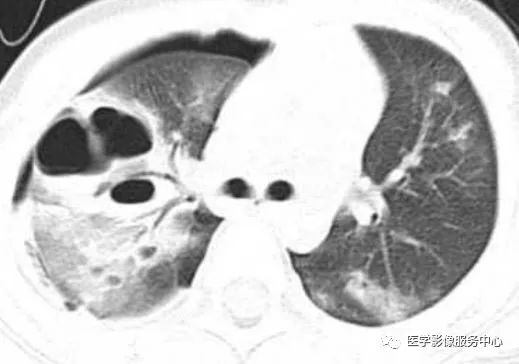

图13a

图13b

图13a,b.为LCH的多发囊肿。表现为不规则形态的奇异含气囊腔,厚壁/薄壁,上肺多,不累及膈角,患者有吸烟史。